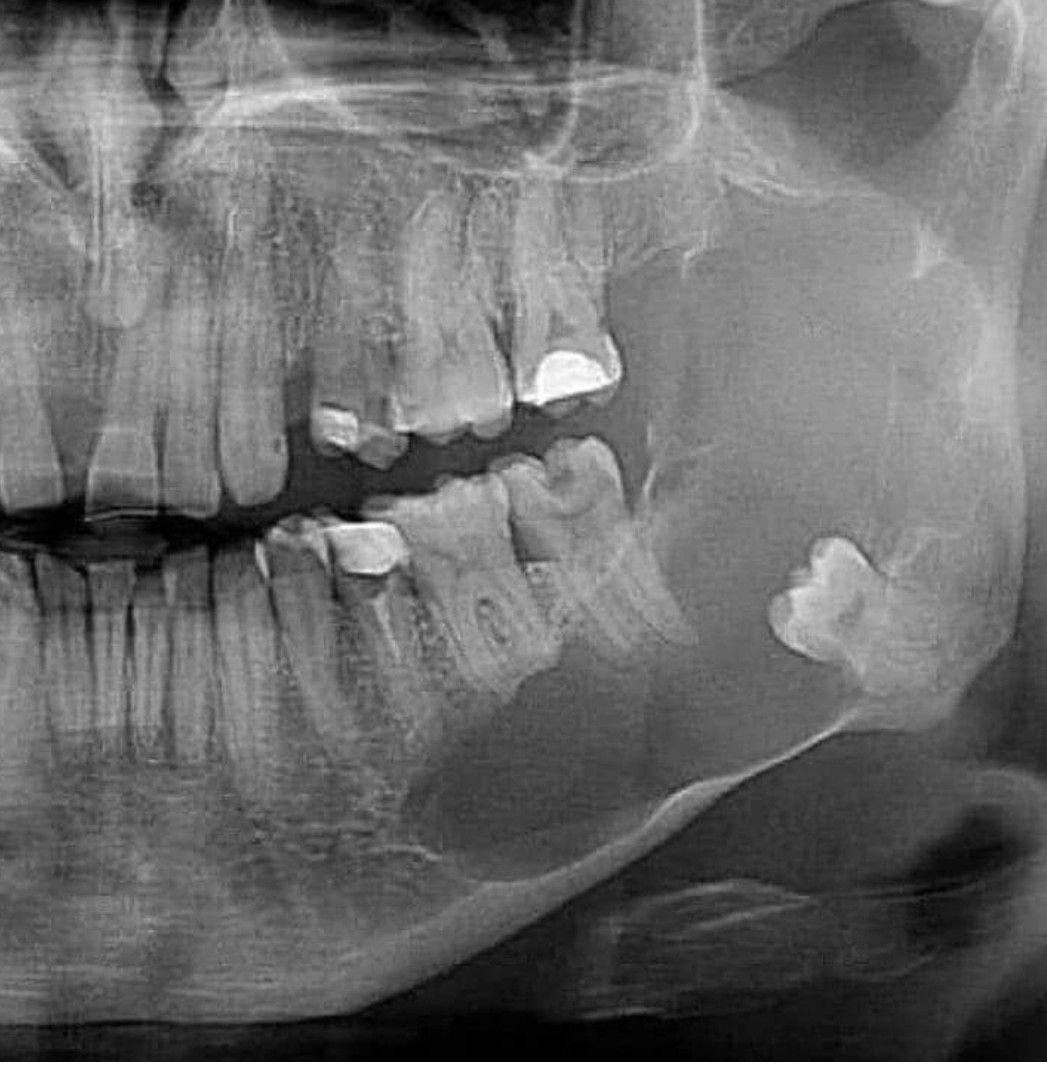

Cyst or Necrosis

What do you think it is?

Cyst

Necrosis

Opg